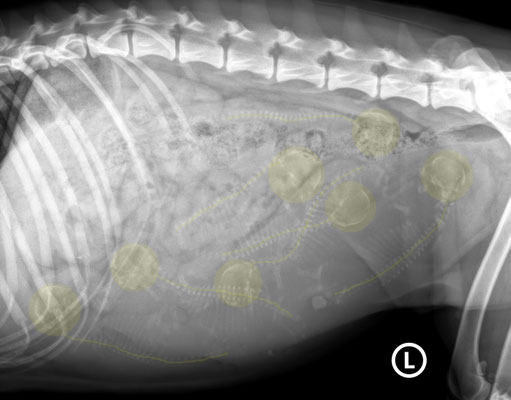

Ab 45 Tagen kann man die Hündin röntgen lassen. Und da sieht man dann mit grosser Zuverlässigkeit die Anzahl Welpen. Im oberen Bild rechts das Röntgenbild vom 1. Juni, Tag 47, aufgenommen mit der neuen digitalen Röntgenanlage der Kleintierklink Laupeneck, unserem "Hausarzt". Deutlich sind die Schädel zu sehen und dann die Wirbelsäule mit den Rippen. Und sie liegen kreuz und quer. Click auf das Bild um es zu vergrössern. Wer's doch nicht so recht erkennen kann: im unteren Bild haben wir die Schädel und Wirbelsäule markiert. Glen hat inzwischen 7 kg zugenommen und wiegt 27 kg.